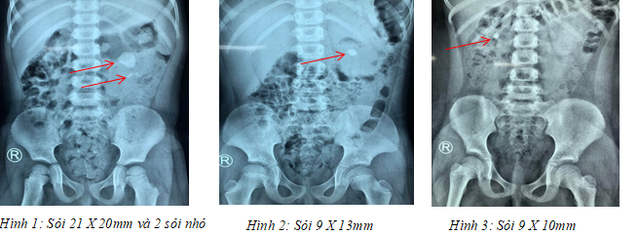

Trước đó, Bệnh viện Bình Dân hấp thu từ bệnh viện Nhi Đồng tại TPHCM các cháu V.N.K. (3 tuổi, ngụ tại TPHCM) có sỏi kích thước 21x20mm cùng 2 sỏi nhỏ ở thận trái; bệnh nhi P.Đ.N.Y. (7 tuổi, ngụ tại TPHCM) có sỏi 9x10mm ở thận phải; bệnh nhi N.T.T.N. (6 tuổi, ngụ tại Cần Thơ) có sỏi 9x13mm ở trận trái.

“Đào” đường hầm siêu nhỏ lấy sỏi thận cho bệnh nhi - 1

Các bệnh nhi nhập viện trong tình trạng bị sỏi thận, điều trị trước đó không hiệu quả